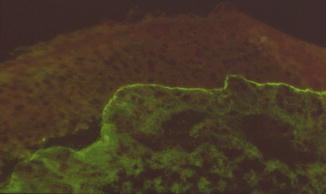

Fig. 35.18

Direct immunofluorescence of nasal mucosa showing linear deposits of IgG along the basement membrane zone and demonstrating the specificity of atrophic rhinitis